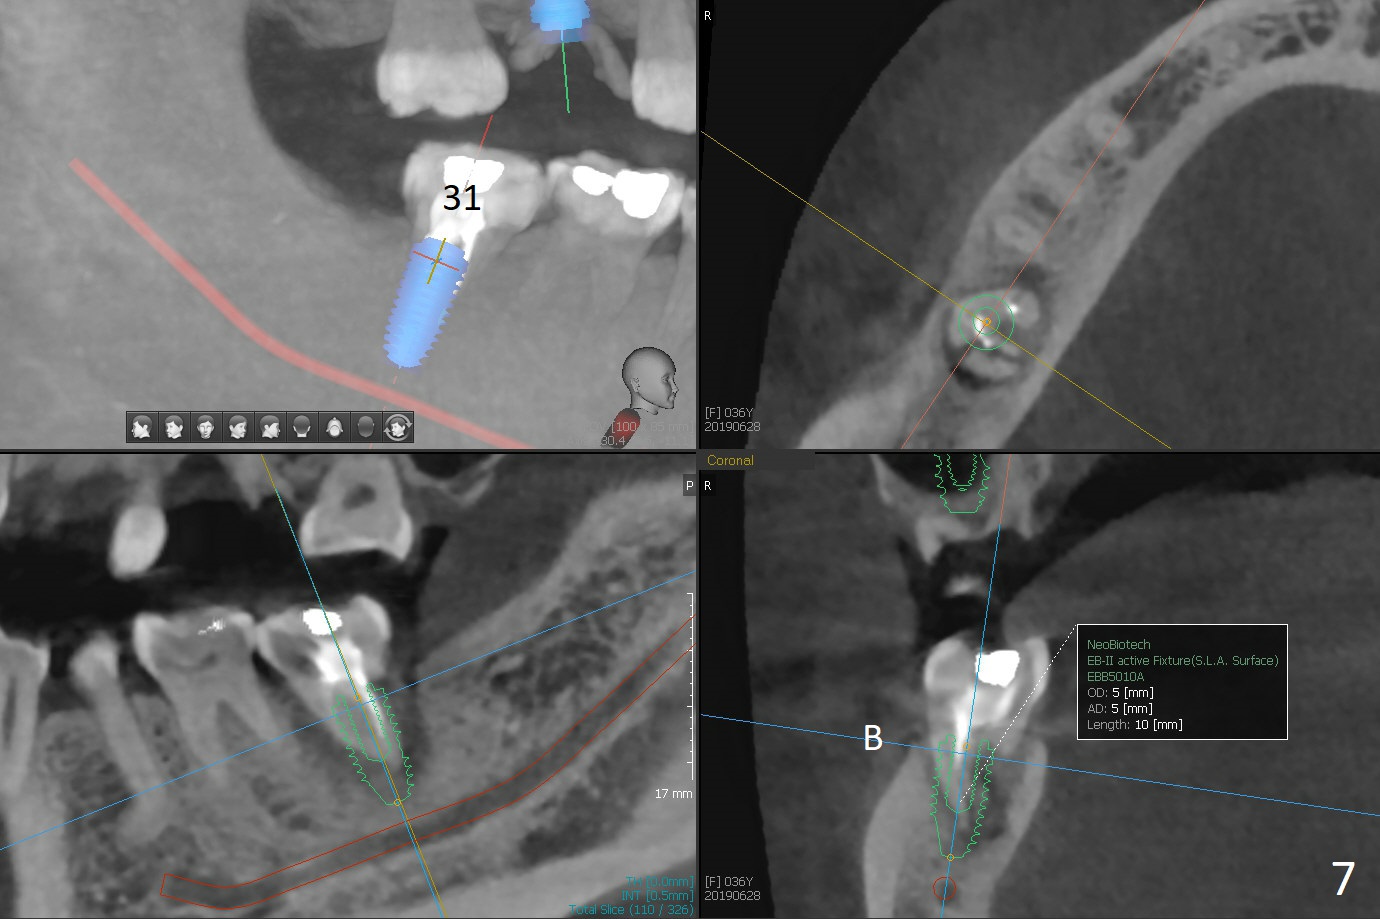

A 36-year-old woman is nervous about dentistry. She will take Valium by herselft before surgery (Fig.1). The tooth #3 has 3 residual roots (Fig.2 (CBCT 3 D occlusal view)). The bone is 2-3 mm thick (Fig.3,4 (sagittal, coronal sections)). A 5x7.3 mm implant will be placed with IS guide (Fig.5 (12 mm offset)). Since IBS implants are able to achieve amazing stability in the thin bone, prepare the shortest 4-5 mm in diameter dummy implants (IS (better surface treatment) and IBS) after sinus lift using UF Guided Sinus Lift Approach Kit (surgery). With intact tooth structure at #14, the bone height is not much (Fig.6), congenital (genetic) in nature. The infection at #31 is more severe (Fig.7). Extraction will be the 2nd in order. Because of limited bone, it is better to do bone graft first. The patient is concerned about the discolored upper right canine, which should be associated with orthodontics 20 years ago (take photos). The apical canal is obliterated (Fig.8,9 arrow) with periapical radiolucency (arrowhead). In fact the bone at #31 is so little that the tooth will be extracted for socket preservation.